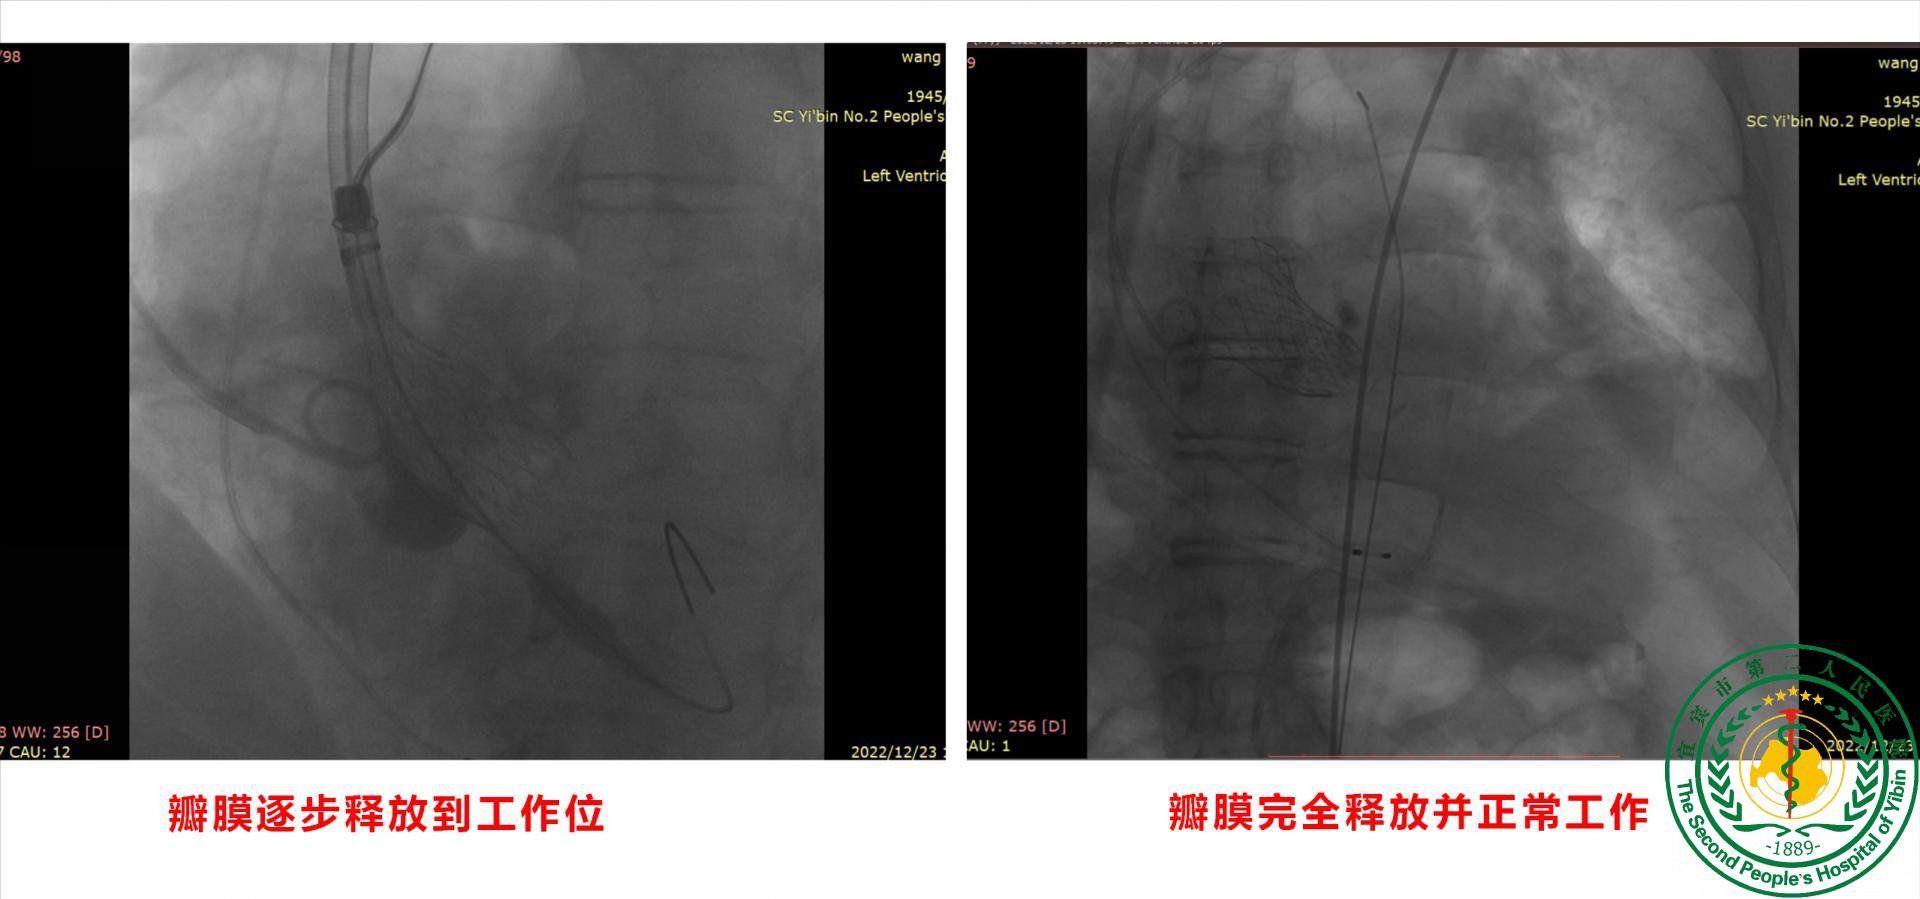

宜宾市二医院成功实施川南首例Evolut Pro瓣膜经导管主动脉瓣置换术(TAVR)挽救极重度主动脉瓣狭窄患者

宜宾市二医院成功实施川南首例Evolut Pro瓣膜经导管主动脉瓣置换术(TAVR)挽救极重度主动脉瓣狭窄患者46787